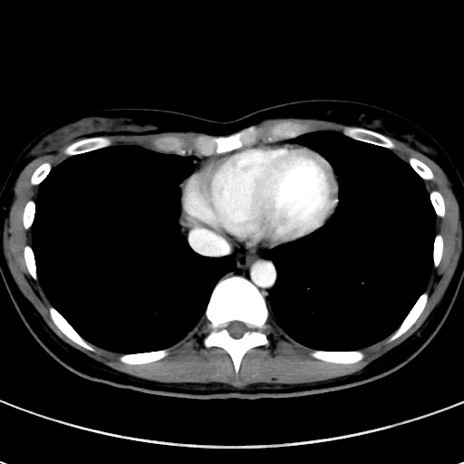

症例17(横断像)

【症例】20歳代女性

【主訴】嘔吐、下腹部痛

【現病歴】昨日夕食後に嘔吐し下腹部痛が出現。本日になっても嘔吐持続し改善しないため来院。

【身体所見】意識清明、BT 37.2℃、BP 108/67mmHg、腹部:平坦、やや硬、下腹部正中から右にかけて圧痛あり、反跳痛軽度あり、tapping pain(+)。

【データ】WBC 13600、CRP 14.94